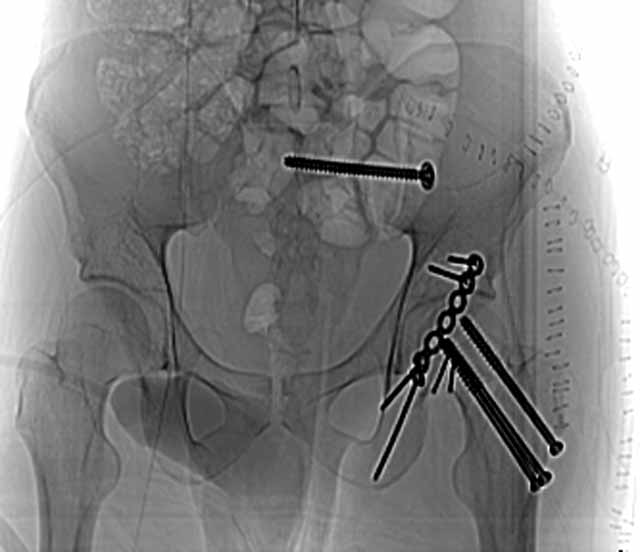

We initially did an ORIF of the femoral neck and then the head using a modified Smith-Petersen exposure with the patient positioned supine. The femoral head fracture fragment was without soft tissue attachments and removed temporarily. The ligamentum teres had been disrupted from its femoral head attachment so it was debrided. The dislocated head-neck fragment was then rotated out of the posterior impaction area, manipulated into the acetabulum preserving it s limited capsular remnants, rotated it to fit the neck, and then stabilized with screws inserted through stab wounds and guided by fluoroscopy. Then we reduced and used small screws to hold the previously removed femoral head fracture fragment.

For a variety of reasons we stopped at that, placed him in traction, and repeated his films and CT.

Two days later we returned to the OR and tried a closed manipulative reduction of the SI joint-iliac fracture but it failed, so we used the lateral (iliac) window of an ilioinguinal exposure to clean, reduce, and clamp the SI joint. We stabilized it with an iliosacral screw and closed.

Under the same anesthesia, we used a prone K-L exposure to reduce the impaction fragment, fold down the posterior wall, and hold it with a plate.

Here are the films....the staple lines mark his incisions.

AP Pelvis

CT Acet

CT SI Joint

We'll use ectopic bone prophylaxis and protect his weight bearing.